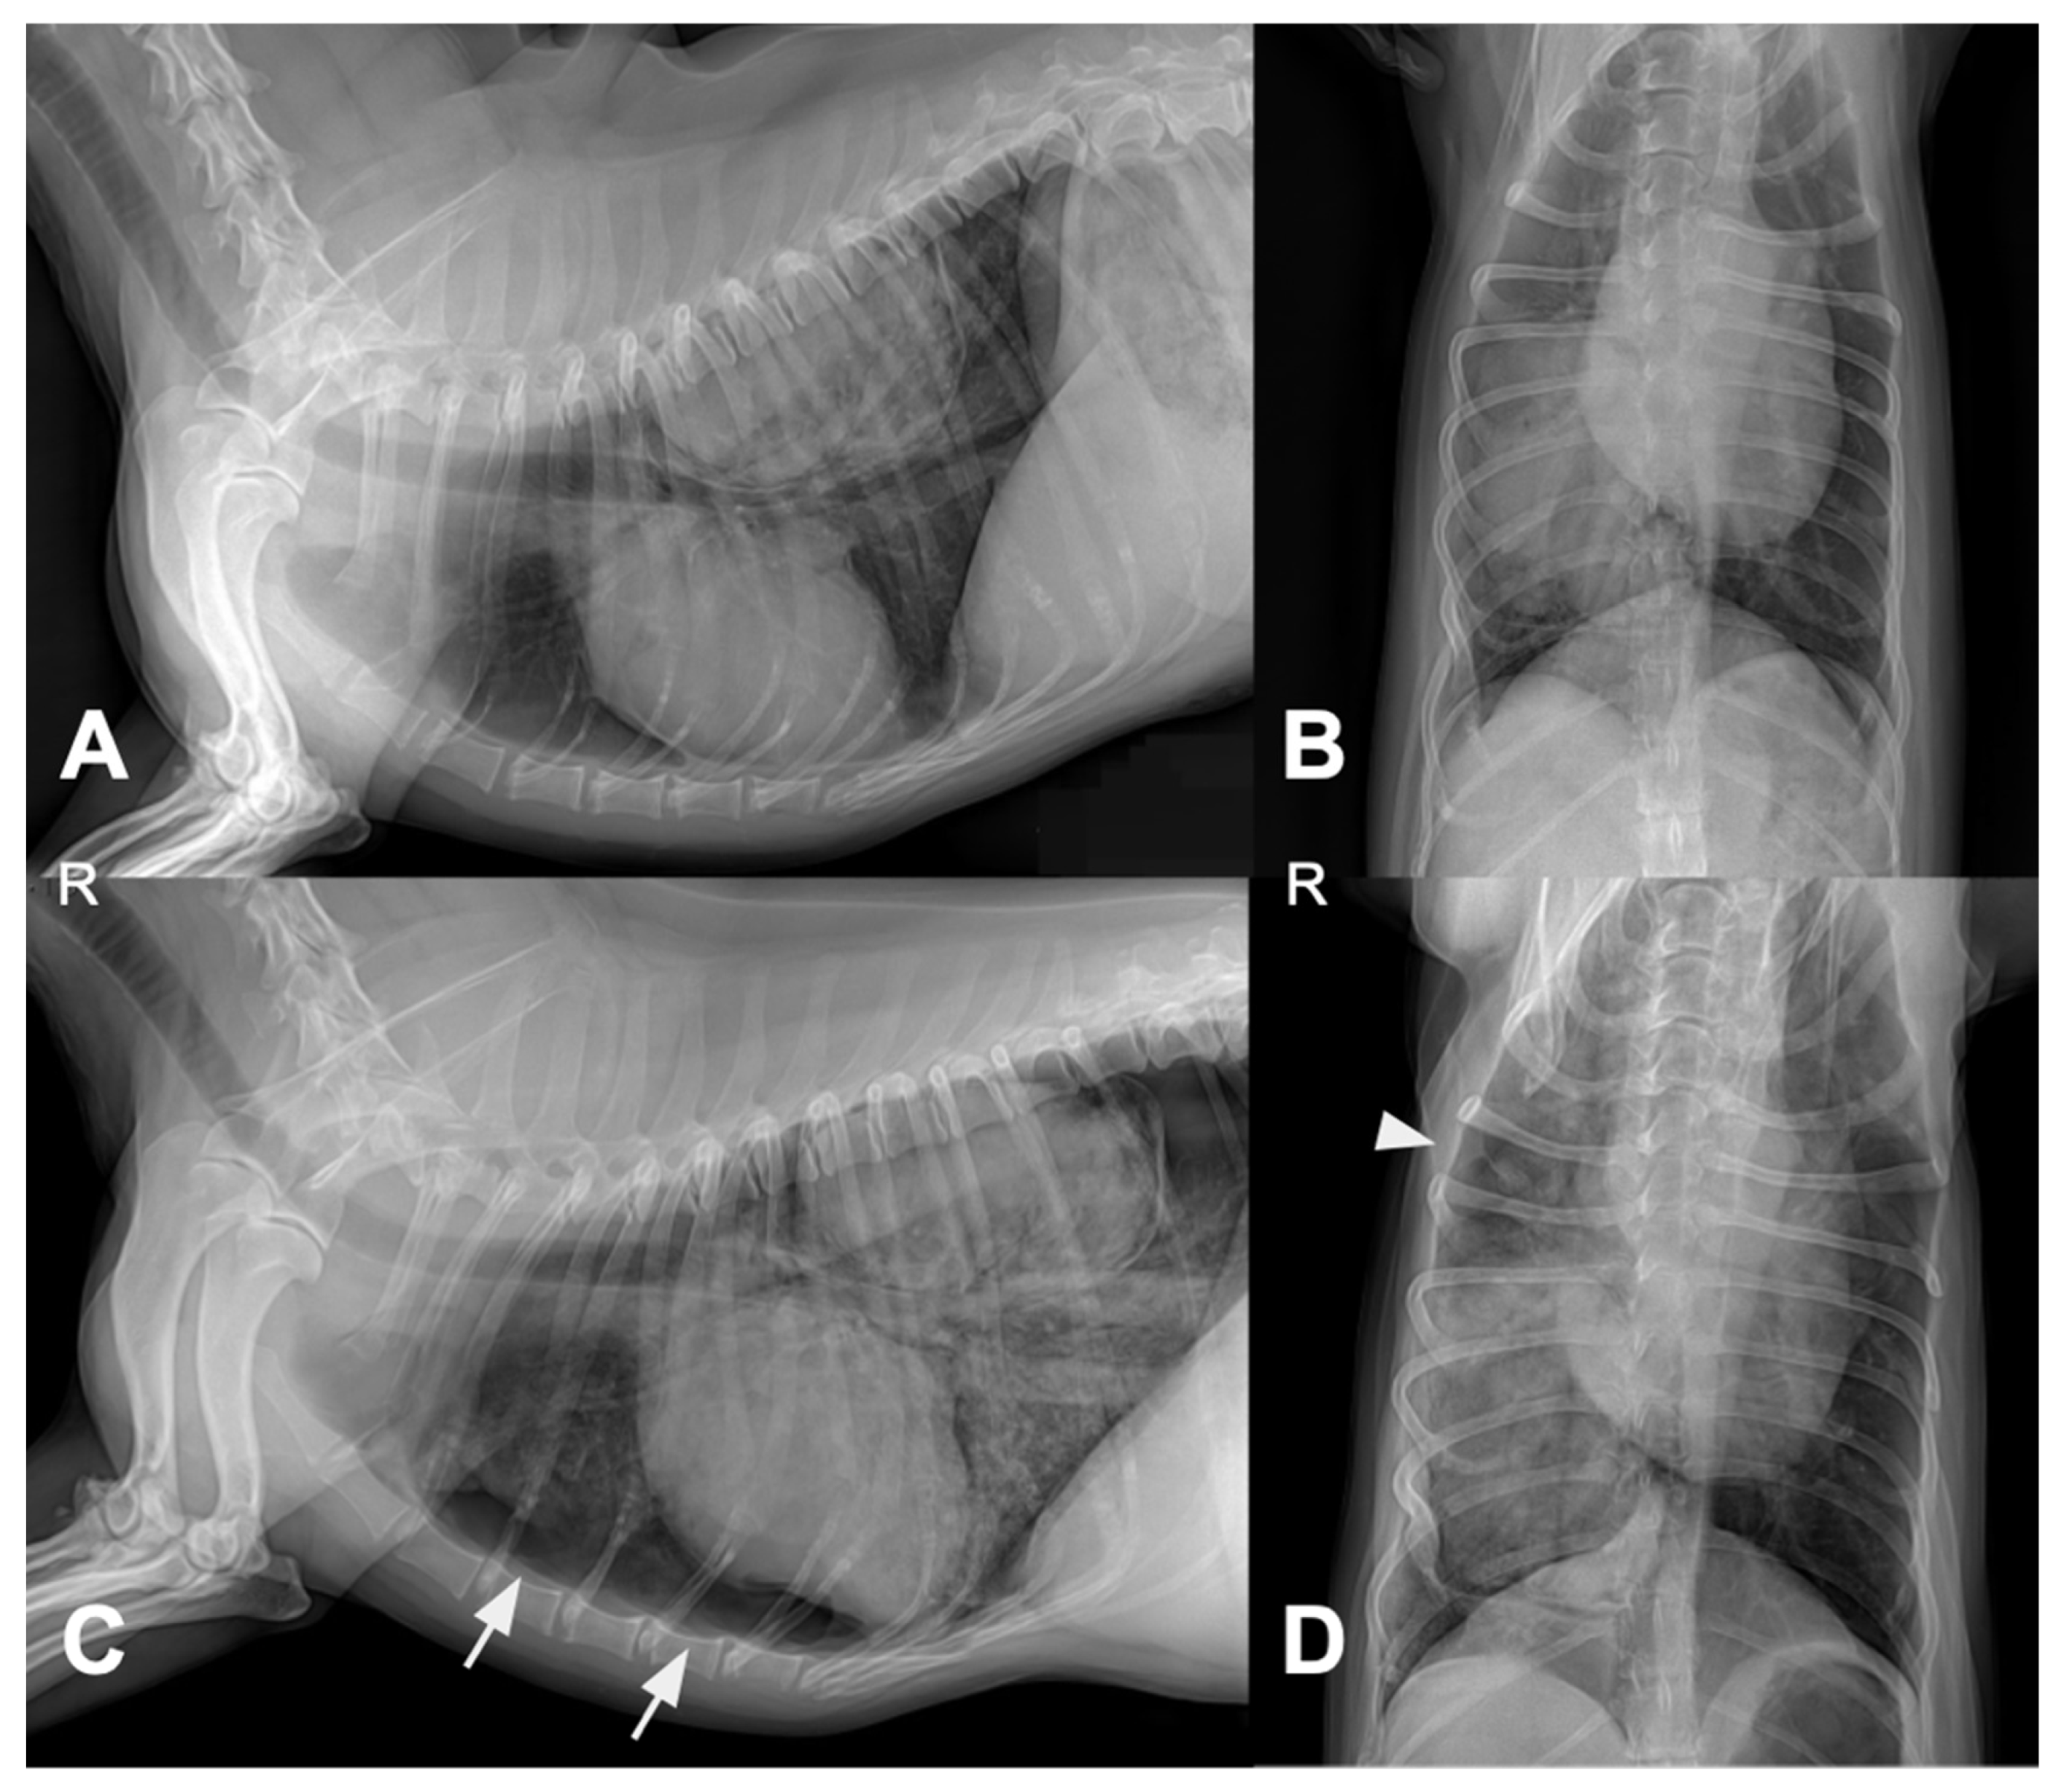

Four days after pulmonary FNA and treatment initiation, thoracic radiography was performed due to acute respiratory distress. Compared with the pretreatment images, follow-up radiographs showed pneumothorax, increased alveolar opacity, and mild pleural effusion (Figure 4).

Figure 4. Thoracic radiographs before (A,B) and four days after (C,D) vinorelbine administration and fine-needle aspiration. Pretreatment images (A,B) show a solitary pulmonary mass without notable perilesional changes. Follow-up images (C,D) demonstrate new abnormalities, including increased alveolar opacity, pneumothorax (arrow in (C)), and mild pleural effusion (arrowhead in (D)). Abbreviations: R, right side.